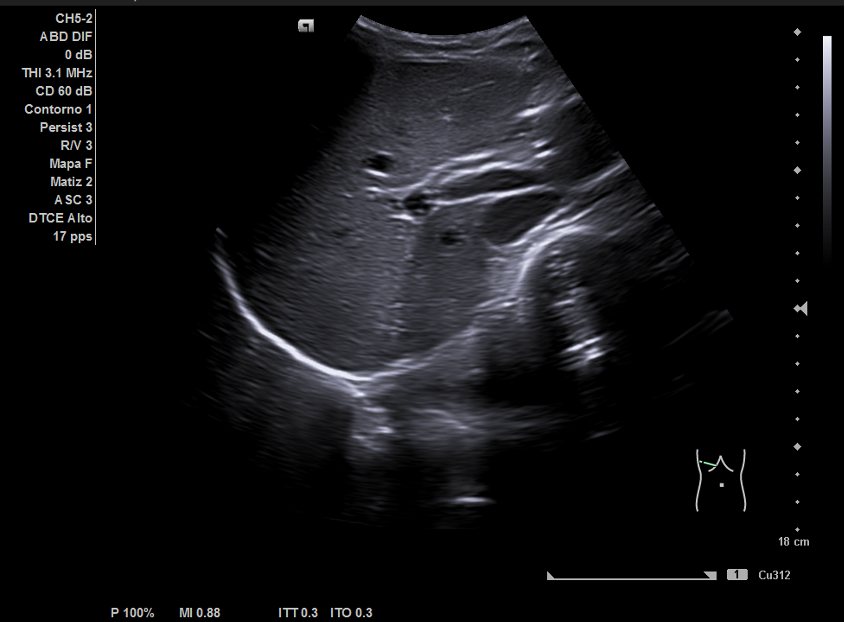

Ecografía abdominal: hígado y vesícula sin alteraciones. Riñones de ecoestructura normales. Útero de características normales. Se apreció imagen anecoica de 7x7 cm que parecía depender de ovario derecho.

En Ginecología se realizó ecografía ginecológica transrectal en la que se confirmó quiste ovárico derecho de unos 79 mm de contenido líquido sin tabiques ni papilas. Con el diagnóstico de crisis de pseudotorsión ovárica se programó para cistectomía de ovario derecho. La anatomía patológica confirmó la presencia de un cistoadenoma mucinoso.